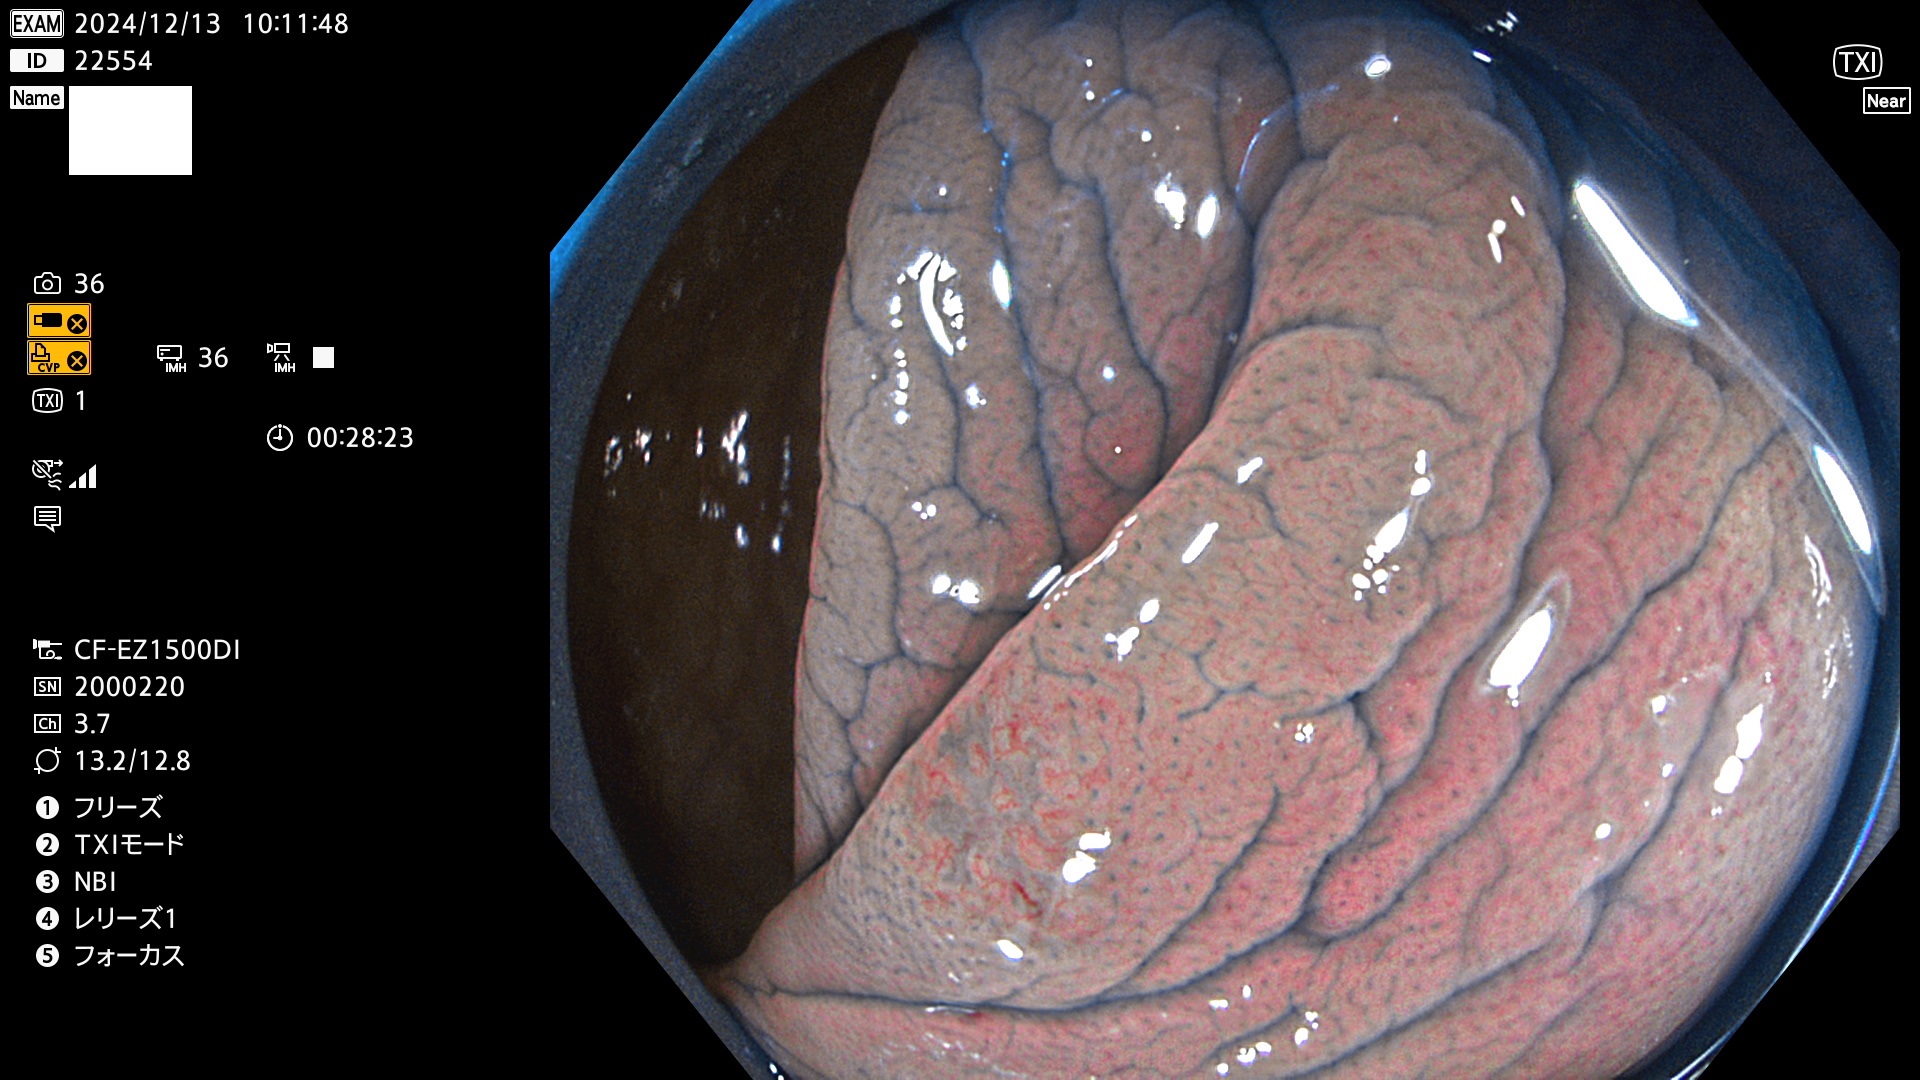

今週のUb、Uc型腺腫

完全に平坦な物をUb、陥凹している物をUcと呼びます。最も発見が難しく危険な病変です。

毎週の検査(木・金・土・日)に発見されたUb、Uc型・腺腫を、その週の日曜の夜にUPし1週間、提示します。

抽出の対象期間 2024年12月12日〜12月16日の5日間(60件の検査)13件 (13/60=21%)